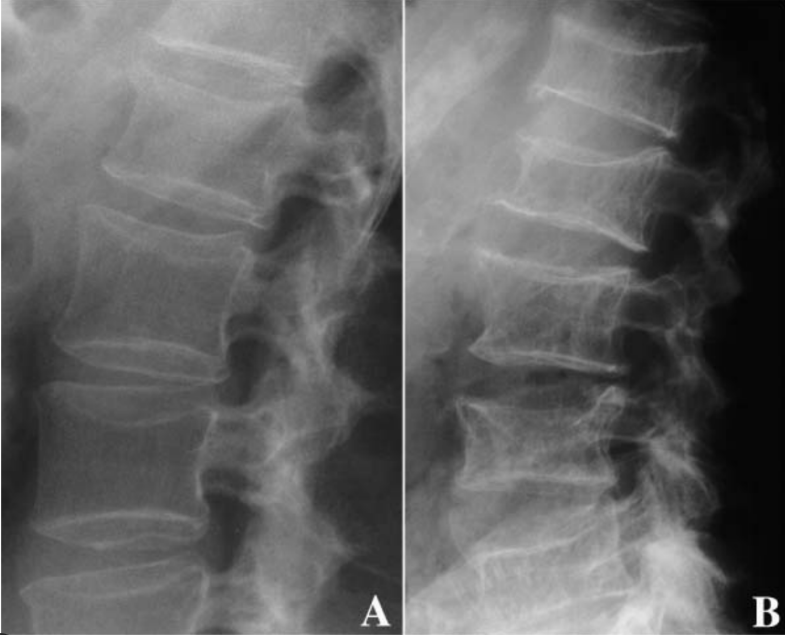

What is abnormal

B shows vertebral fractures since the anterior part of vertebrae is collapsed compared to posterior part